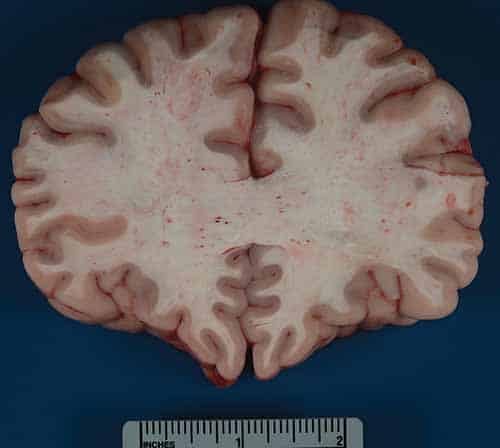

In cases of FES, external examination may be notable for a petechial red-brown rash involving the head, neck, anterior thorax, axillae, and/or conjunctivae. On internal examination, pulmonary and cerebral petechiae may be apparent. The central nervous system petechiae are typically most pronounced in the white matter (Figure 24-8) and spinal cord. A thorough histologic sampling is advised. While subclinical resuscitative fat emboli are frequently seen in the pulmonary vasculature, widespread systemic involvement (e.g., brain, skin, kidney) may suggest FES. Histologic sections of the rash may show round to ovoid vacuoles occluding small dermal capillaries with resultant erythrocyte extravasation, and similar intravascular vacuoles can typically be seen in multiple tissue types (Figures 24-9 and 24-10). To distinguish whether vacuoles represent fat versus air emboli, confirmatory fat stains can be performed. Lipids are dissolved by standard tissue processing solvents; however, stains including oil red O (stains fat red), Sudan black (stains fat black), or Sudan III (stains fat orange) can be performed on frozen section tissue (Figures 24-11 and 24-12). Alternatively, post-formalin tissue fixation methods involving osmium tetroxide or linoleic acid/chromic acid can be employed.